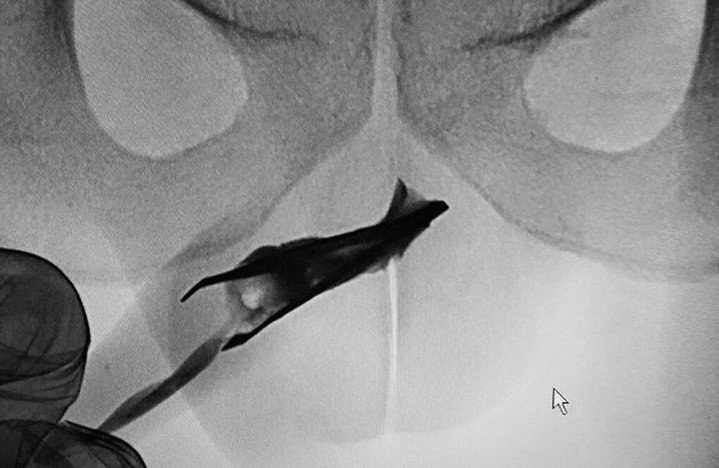

یک موچین ۸ سانتیمتری، چهار سال در مجرای ادرار یک مرد جوان ۲۲ ساله در عربستان سعودی گیر کرده بود. این جوان ادعا کرد که هیچ مشکلی، مثل عفونت و تب نداشت و راحت ادرار می کرد. هافینگتون پست نوشت در موارد خیلی نادر، برخی مردها برای ارضای جنسی یک شی خارجی وارد مجرای ادرار خود می کنند!